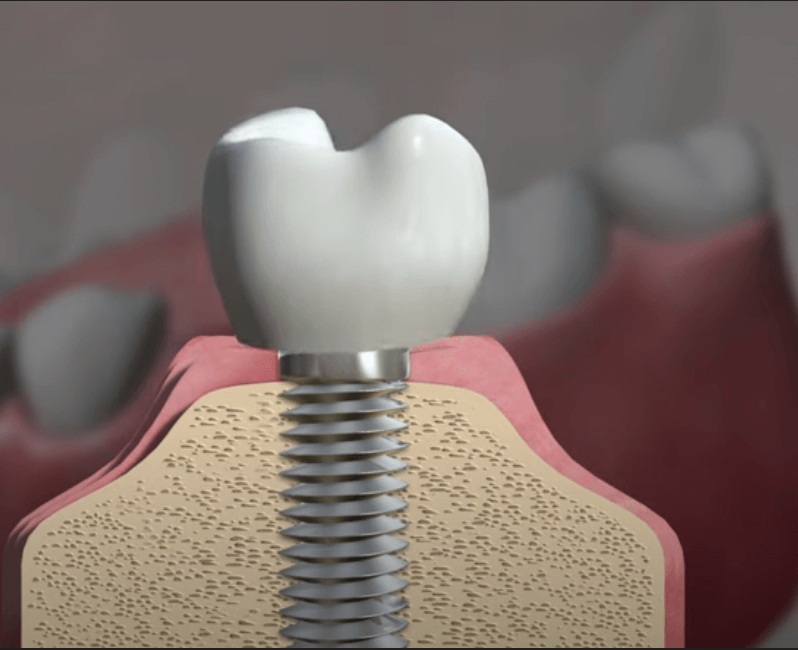

만약 임플란트가 흔들린다면, 이는 크게 두 가지 주된 원인으로 나뉩니다. 첫 번째로는 임플란트를 구성하는 나사가 헐거워져서 풀어지는 경우입니다. 이 경우에는 나사를 다시 적절히 조이면 문제를 해결할 수 있으며, 비교적 간단한 조치로 신속한 치료가 가능합니다. 그러나 두 번째로, 임플란트 주위염이 원인인 경우에는 상황이 다릅니다. 임플란트 주위염은 임플란트와 치조골 사이의 골 결합이 파괴될 때 발생하며, 이 경우에는 임플란트를 다시 수술하여 재픽싱하는 것이 필요할 수 있습니다. 이는 좀 더 복잡한 치료를 필요로 하며, 빠른 대응이 요구됩니다. 따라서 임플란트의 느슨함이 발견되면, 원인을 신속히 확인하여 적절한 치료 방법을 찾는 것이 중요합니다.

임플란트는 현재로서 자연 치아를 대신할 수 있는 가장 효과적인 방법 중 하나로 인정받고 있습니다. 그러나 임플란트 주위염이 발생하면 임플란트를 제거하고 재식립하는 과정은 간단하지 않기 때문에 초기부터 신중한 관리가 필요합니다. 특히 정기적인 치과 검진이 매우 중요한데, 외부적으로는 문제가 없어 보이더라도 실제로 치조골이 손상되어 있는 경우가 있을 수 있습니다. 따라서 치과 전문의의 꾸준한 감독과 세심한 관리를 통해 임플란트가 오랜 기간 동안 튼튼하게 유지될 수 있도록 하는 것이 핵심입니다.

임플란트는 충치가 발생하지 않지만, 주위염이 발생할 수 있는 가능성이 있으므로 구강 위생 관리는 철저히 이루어져야 합니다. 따라서 개인은 자신의 구강 건강과 위생에 대한 관심을 기울이고, 올바른 칫솔질 습관을 통해 꾸준한 관리를 유지하는 것이 중요합니다.